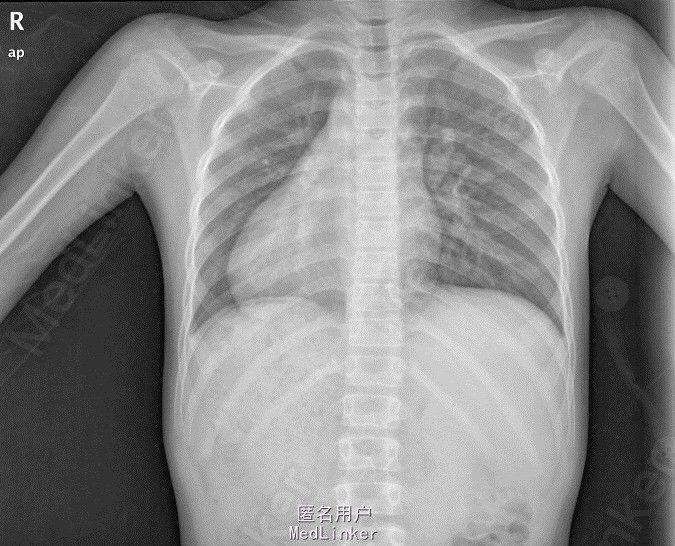

【病例】两肺纹理结构清晰,右位心,右膈下可见胃泡影

300x408 - 18KB - JPEG